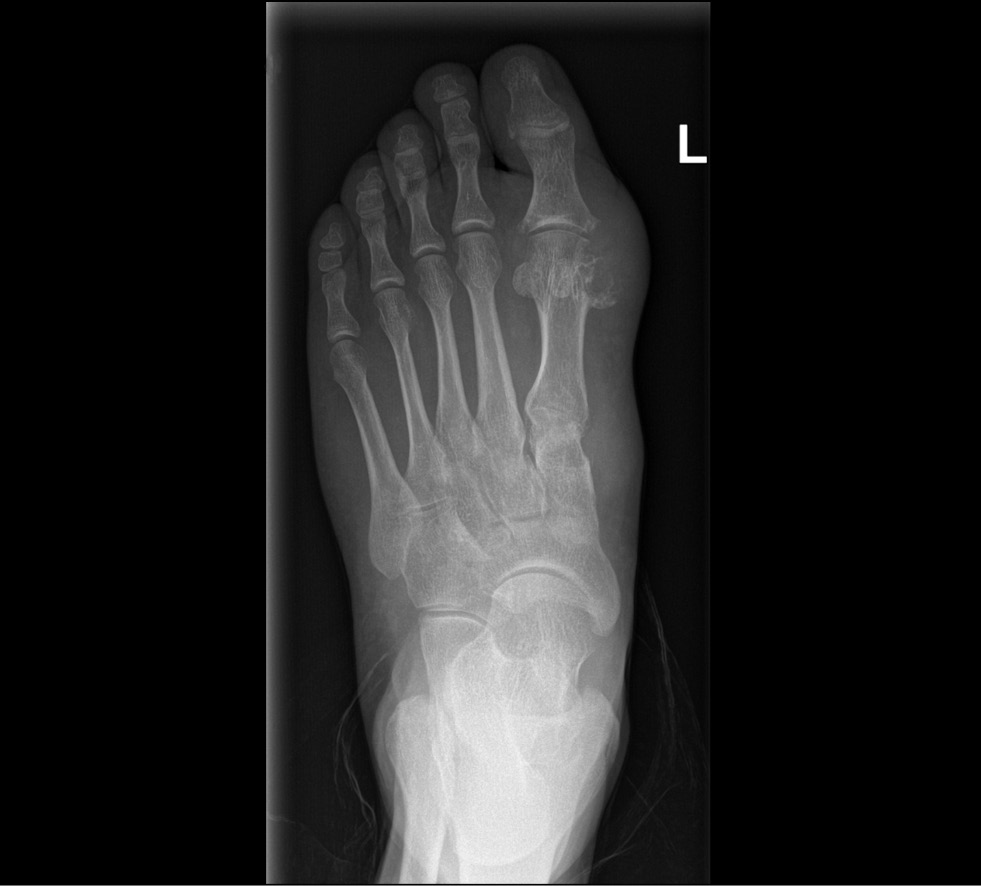

Typical radiographic signs of gout are punched-out bone erosions with sclerotic contours and overhanging borders, also known as “rat bite” or “gull wing” erosions (Fig. 1).

Fig. 1. Bone erosions in a patient with gout (radiography findings of the Medical Research and Education Center of the Lomonosov Moscow State University).

Articular tophi, which resemble inhomogeneous soft tissue indurations, can be seen in chronic gout. X-ray changes are seen several years after gout onset and may be useful in confirming the diagnosis later in the disease progression [16, 17].